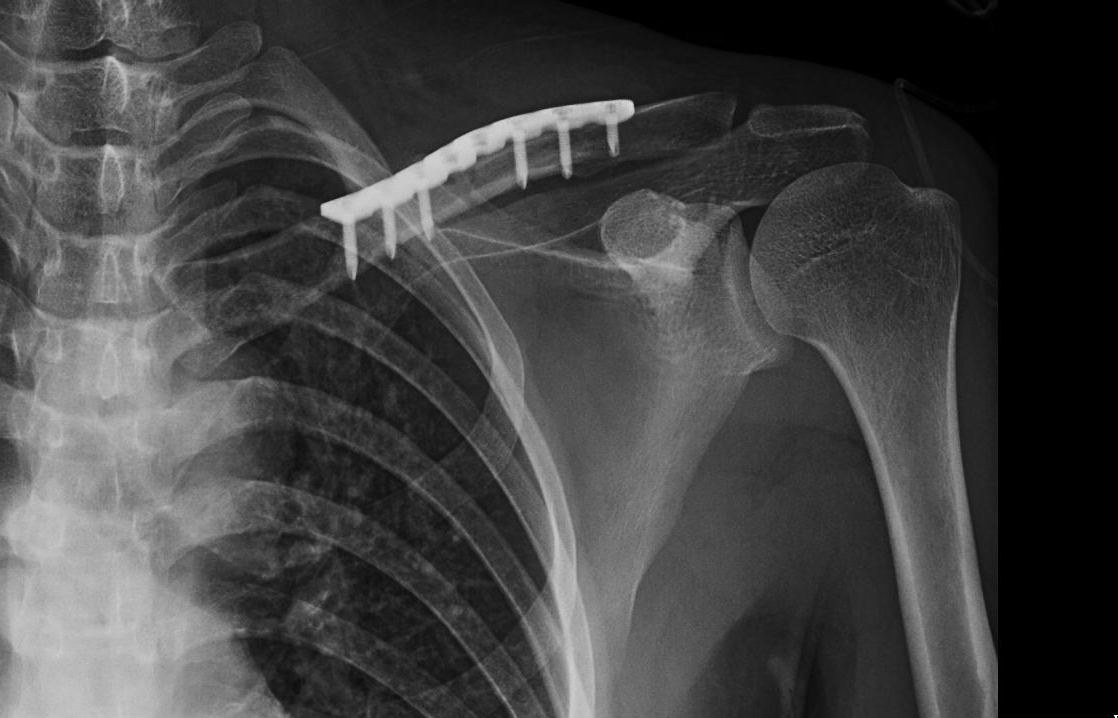

- 术中应注意锁骨有上下、前后、旋转三种运动形式,骨折复位时除了注意锁骨轴向稳定外,骨折断端各需3枚螺钉以控制旋转,避免内固定失效。

- 手术患者发生骨不连往往与内固定不稳定及软组织损伤导致血供破坏有关,对于简单骨折,尽量在骨折断端应用拉力螺钉加压固定。

- 锁骨中部血供主要来源于骨膜的血管(胸肩峰动脉的分支),自胸大肌和三角肌附着处进入,手术中应尽量较少骨膜剥离。

- 对于锁骨远端骨折应用锁骨钩钢板时,骨折近端至少要用3枚螺钉固定。术后三角巾悬吊6周,每日至少取下三角巾5次,做肩关节钟摆、划小磨运动。6周后去除三角巾,肩关节开始做肩关节全范围功能锻炼。